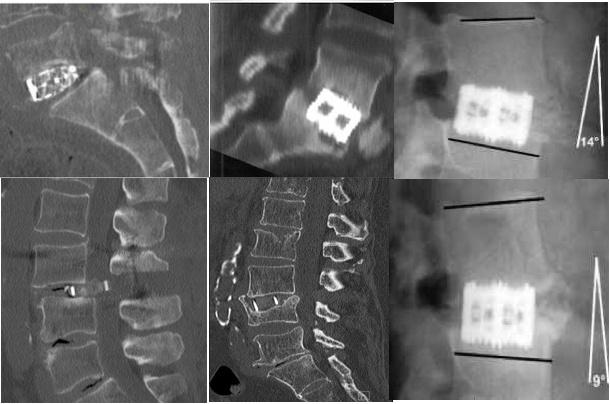

但是,由于D/XLIF技术是采用经腰大肌入路,一些入路固有并发症则无法避免,如腰大肌血肿,腰丛神经损伤(运动障碍 0.7–33.6%,感觉障碍 0–75%);L5/S1受髂骨阻挡,神经电生理检测假阴性,只能通过撑开椎间隙获得间接减压,以及有时需附加钢板或后路手术等问题经常困扰术者[14]。为减少上述问题,OLIF技术应运而生。2012年,Silvestre提出了OLIF(Oblique Lumbar Interbody Fusion),其优势在于:腰大肌外操作,避免血肿及腰丛损伤;植入物倾斜放入,不需过度牵拉血管;植骨块大、椎间高度和前凸恢复好[15]。其不足包括:肋弓(L1-3)和髂骨(L5/S1)阻挡;向前牵拉交感神经—损伤可能;只能获得间接减压;需附加后路手术。

笔者及团队自1998年起开展了腹腔镜下腰椎融合技术,该技术可以说是现代OLIF技术的全内镜下的“版本”。然而,在临床应用过程中,腹腔镜锁孔下操作存在着上述诸多问题,为兼顾微创的同时改善手术的便利性与实用性,2002年起,腰椎前路融合手术均革新为腹腔镜辅助小切口或单纯小切口方式进行。在融合器稳定性方面,由于早期缺乏自稳装置,前路术后往往需要进行后路补充固定。近年来,随着理念的进步和经验积累,涌现了附有自身稳定的融合器如LDR等。为此,结合自锁cage的应用,于2015年设计了腹前外侧入路腰椎间融合(ALLIF)技术,该入路设计简单、直接、安全。术中患者采用斜卧位,切口根据椎间隙的体表投影,贴腹直肌左外缘作4-6cm横/斜切口所经层次:腹外斜肌-腹内斜肌-腹横肌至腹膜外间隙,用常规腹部拉钩将血管及腹膜稍牵向内侧,另一拉钩置于椎体侧前、交感神经链前方,将其稍向后牵开。辅以头灯放大镜或显微镜,直接对神经结构进行减压,选用自锁型融合器,不需附加前路钉板或后路钉棒,同时对于退行性滑脱的病例,采用前侧入路方式可以获得有效的椎体复位,从而达到减压、复位、融合与稳定等“四位一体”,“一箭多雕”之目的[16,17]。